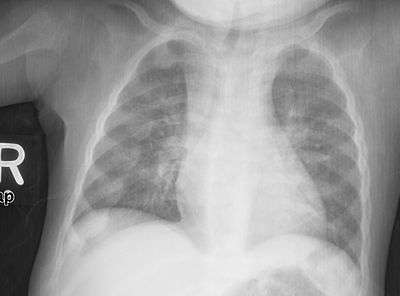

An X-ray or radiograph of an advanced sufferer from rickets tends to present in a classic way: bow legs (outward curve of long bone of the legs) and a deformed chest. Changes in the skull also occur causing a distinctive "square headed" appearance (Caput Quadratum). These deformities persist into adult life if not treated. Long-term consequences include permanent bends or disfiguration of the long bones, and a curved back.[6]